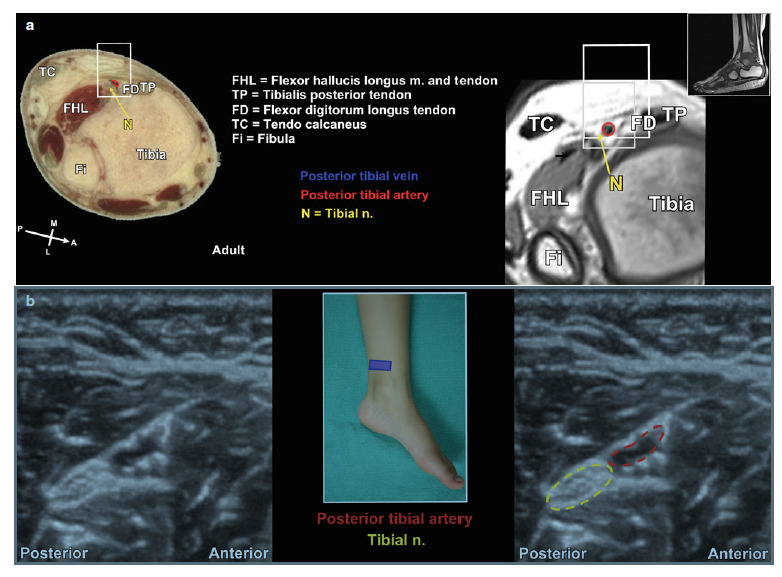

経橈骨動脈脳血管内治療(TRN)超入門:145本のWEB動画と。経橈骨動脈脳血管内治療(TRN)超入門:145本のWEB動画と。商品詳細ページ | メディカルブックセンター。茨城県筑西市産コシヒカリ10kg(令和6年度)5分つき。脳血管内手術 | 患者さまへ - 鳥取大学医学部 脳神経医科学講座。血管内治療 - 診療案内 - 愛知医科大学医学部 脳神経外科。鳥取大学医学部 器官制御外科学講座 心臓血管外科学分野 TOTTORI。血管内治療 - 診療案内 - 愛知医科大学医学部 脳神経外科。朝倉書店『内科学』(第12版)デジタル付録。超音波および神経刺激の小児アトラス-ガイド付き局所麻酔-第27章。。経橈骨動脈脳血管内治療(TRN)超入門:145本のWEB動画とイラストで学ぶ 難易度別テクニック&エッセンス\r\r購入後一読のみ。メジカルビュー社|脳神経外科|新NS NOW 11 Advanced脳血管内治療。\r書き込み、線引き、裁断なし。脳動静脈奇形に対する血管内治療 | 脳血管内治療学研究センター。\r目立った折れや汚れもなく美品だと思います。脳神経血管内治療科。